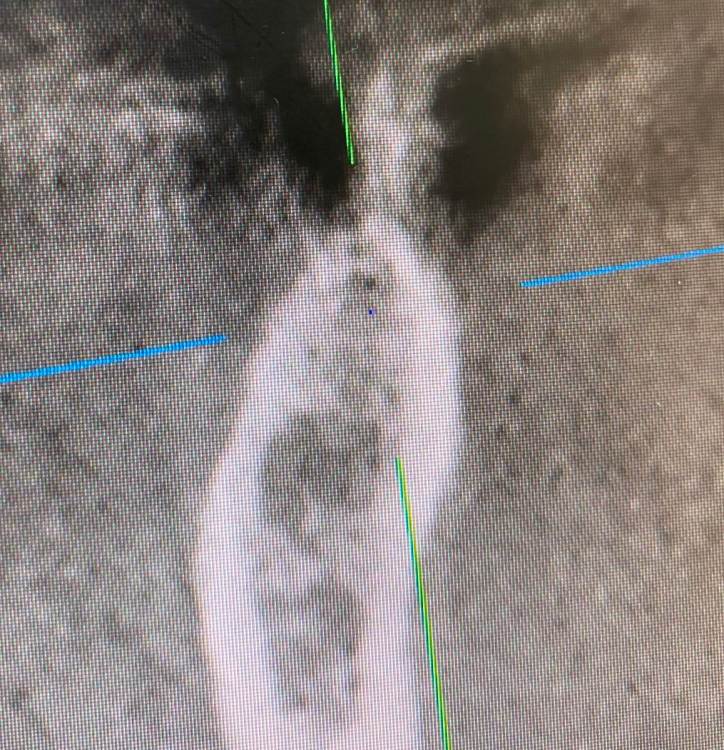

колесников Опубликовано 6 июля, 2022 Поделиться Опубликовано 6 июля, 2022 Здравствуйте коллеги! Впервые вижу перелом Астры. Впервые получил перелом «своей»Астры. Вероятно ещё никто не видел перелом Астры профайл. Диаметры 4.5 и 5.0. Самое неприятное что это произошло за 1,5 года. Ошибка протезирования. Перегруз. Резорбция. Фрактура. Из интересного. Одновременно с имплантацией была произведена контурная пластика поднадкостнично,графт шурос. Это работает. Ставим галочки и двигаемся дальше. 2 1 1 Ссылка на комментарий

колесников Опубликовано 6 июля, 2022 Автор Поделиться Опубликовано 6 июля, 2022 5 часов назад, Aquarius сказал: Спасибо за столь познавательный кейс!!! Я где- то читал, что вроде как перегруза на полностью интегрированных имплантах быть не может. Вроде как первично надо высвободить какую-то площадь импланта от кости ( воспаление, резорбция) чтобы он треснул. А не наоборот. Автор сего высказывания ссылался на то, что в связке имплант-коронка есть куда более слабые места , чем стенка интегрированного импланта. Например, фиксирующий винт. Для конического соединения это утверждение не применимо. Очень часто получаем холодную сварку имплант-абатмент,винт совершенно не работает. Протокол отработан как автомат Калашникова,платформа относительно Зенита и вершины гребня,высота уступа,наличие и ширина прикреплённой слизистой. Далее процесс запускается вспять и через два года наблюдаем прирост кости на скосе гребня. Радиальная Резорбция в виде кратера это всегда перегруз. Импланты не болят. Вокруг них нет посредника-связки,нет проприорецепции. Между тем диссонанс окклюзии со временем нарастает,тк зачастую имеются разнородные по плотности материалы в полости рта. Отчасти пациент тут виноват,не продолжил лечение,пропал на год. Но основная вина ортопеда. Причина личная. Коронка на 45 осталась от старого моста,44 вовсе пародонтитный. Желая их «спасти» вывел из прикуса,основная нагрузка справа упала на импланты. Третий сектор провисший мост 34.35-38 с подвижными 34,35 ,оставлен не тронутым. Хорошая хирургия пошла в утиль по причине малодушия. В итоге когда я стал все это разматывать и рисовать перспективы,пациент сам настоял на тотальной работе. Слабину не даём,за всеми следим. 1 Ссылка на комментарий

TIGER Опубликовано 11 июля, 2022 Поделиться Опубликовано 11 июля, 2022 тут ожидаемо,недозаглуб,grade4 конус ....и закономерный финал,иесли там винтовая с уровня имплантов то вообще картина маслом Ссылка на комментарий

Irouil Опубликовано 11 июля, 2022 Поделиться Опубликовано 11 июля, 2022 (изменено) Не понял - почему недозаглубен? Оба винтыа где-то на 1мм под краем гребня Изменено 11 июля, 2022 пользователем Irouil Ссылка на комментарий

Irouil Опубликовано 11 июля, 2022 Поделиться Опубликовано 11 июля, 2022 (изменено) По фото невозможно понять что там было заглубленно и что нет, на рентгене картина объективнее Я вижу из возможных косяков пл хирургии только избыточно лингвальное позиционирование платформы у одного из винтов, из-за чего стенка очень тонкая - если там случилась резорбция, то иллюзию недозаглубения на фото она вполне может создать К тому же, ТС раньше рассказывал что часто идёт на тунельную твердотканную аугментацию при имплантации в таких случаях, если тут тоже - то для меня неточное позиционирование объясняется именно тунельным подходом и ограниченным обзором по такому поводу. Это, в сущности, единственное, что останавливает меня самого попробовать подобную аугментацию как альтернативу минисосиджу. Но надо услышать ТС, это только мои догадки Изменено 11 июля, 2022 пользователем Irouil Ссылка на комментарий

Astronaft Опубликовано 12 июля, 2022 Поделиться Опубликовано 12 июля, 2022 (изменено) 06.07.2022 в 14:28, колесников сказал: Протокол отработан как автомат Калашникова,платформа относительно Зенита и вершины гребня,высота уступа,наличие и ширина прикреплённой слизистой. Далее процесс запускается вспять и через два года наблюдаем прирост кости на скосе гребня. Это хорошай заговор-пожелание. В жизни часто не так. По одной простой причине общее здоровье человека влияет намного сильнее. Пародонтологический статус - если есть карманы хоть 5-6мм где-то во рту риск пери-имплантных явлений возрастает. Микробиота слюны, вязкость, диета, качество гигиены, обший воспалительный фон- это сфера влияния пациента. Качественное местное исполнение это хороший фундамент - только одна из составляющих. Астра Профаил - укороченный, асимметричый конус. 3мм с одной стороны, 2мм с другой. Конфигурация перелома закономерна - сами абатменты раскололи высокую стенку от низкой. Я бы предположил что тещины первичны, резорбция это следствие. Изменено 12 июля, 2022 пользователем Astronaft 2 4 Ссылка на комментарий